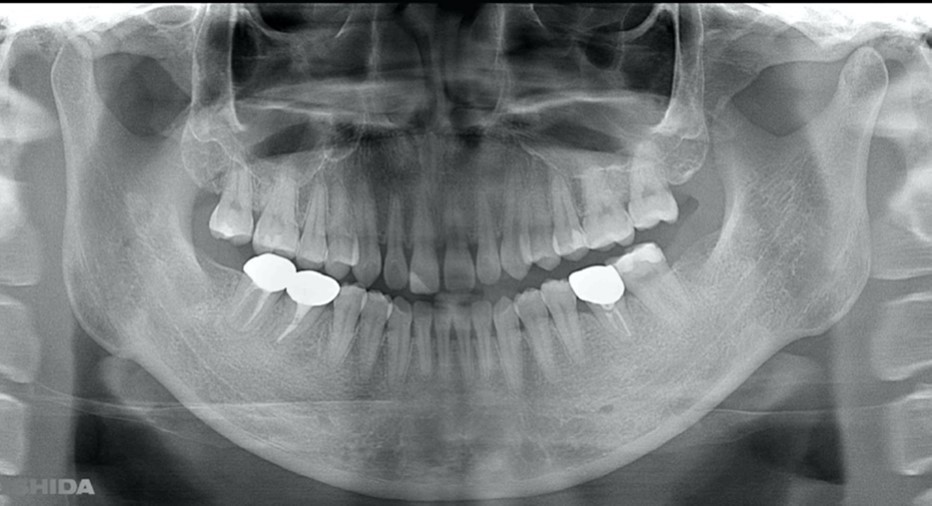

A 27-year-old female patient came to us with discomfort in the right lower jaw (Figure 1). Her primary symptoms were pain in the lower right tooth when biting and discomfort associated with not being able to chew well with the lower left single denture. The patient was married and had one young child, and previously received dental treatment in China, then had returned to Japan for childbirth and early childcare. The patient was a nonsmoker with moderate plaque control and medical history taking revealed no problems. In clinical and radiographic examinations, a root fracture was observed on tooth #46, which had been endodontic ally treated and restored with a full-cast metal crown. Periodontal probing revealed a pocket depth of 8 mm on the buccal center side of the tooth. No pain was detected with percussion and mobility of the tooth was normal. (Figure 1, Figure 2, Figure 3).

Figure 1.Clinical case of right auto transplantation. Panoramic view at initial examination.Tooth #46 was shown to be half decayed and a cystic lesion was found in the mesial root apex. Tooth #36 was lost, while #48 and #38 were present. There was a total of 29 teeth in the oral cavity.

Figure 2.Pre-treatment X-ray findings. A cystic lesion was found in the mesial and distal roots apex, and root nodule of #46.

Figure 15.Panorama X ray image obtained one year after procedure for #36. The transplanted teeth demonstrated good function.